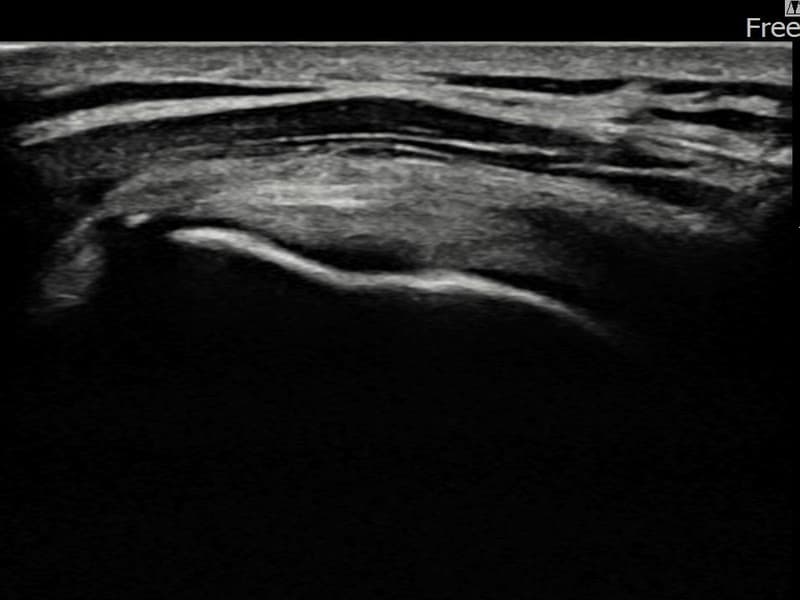

施術後

術前超音波にて左 棘上筋腱 部分断裂・左肩棘上筋腱のエコー不連続と腱欠損(7mm × 3mm (腱厚の約30%欠損))を確認。術後超音波では断裂部位が再生組織で充填され、腱の連続性回復とエコーパターンの正常化が確認されました。

持続する左肩痛で来院された患者様です。超音波検査にて左 棘上筋腱 部分断裂(欠損:7mm × 3mm (腱厚の約30%欠損))を確認し、超音波ガイド下で非手術的縫縮術を施行しました。術後は約4〜6週間のブレース装着の後、段階的なリハビリプログラムを実施。経過超音波で腱の連続性回復を確認し、患者様は無事に日常生活へ復帰されました。